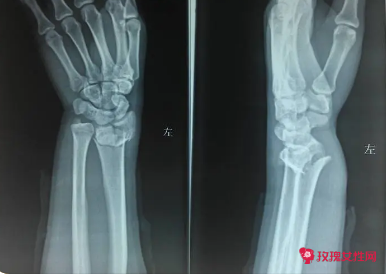

骨折的功能锻炼的目的及方法

骨折后期需要在专业的康复师指导下进行运动训练,作业训练等康复功能锻炼,不要进行剧烈的运动,要注意休息,骨折一般需要6个月左右才能恢复好的。可以配合这些物理治疗,比如照射红外线灯,艾灸等治疗,可以多用热毛巾热敷同时配合按摩。

如果发生骨折,骨折后进行的康复运动类型与骨折的位置、骨折的严重程度和治疗方法有关。例如患者发生手掌掌骨骨折,骨折端移位不大,可通过石膏夹持外固定进行保守治疗,一般骨折后2周患肢的手指可适当活动,可使局部肌肉收缩舒张,锻炼肌肉防止肌肉萎缩。骨折1个月左右可以撕开石膏,适当活动手腕来恢复活动功能。

骨折病人功能锻炼的目的和原则

首先要根据骨折的严重程度,如果是轻度的骨折没有出现骨折移位的情况下,恢复时间会比较快,大概三到四个月就会有明显的骨痂形成,可以适当地进行康复训练,如果粉碎性骨折可能需要一年以上的时间才能够适当的训练,所以具体情况要具体判断的。